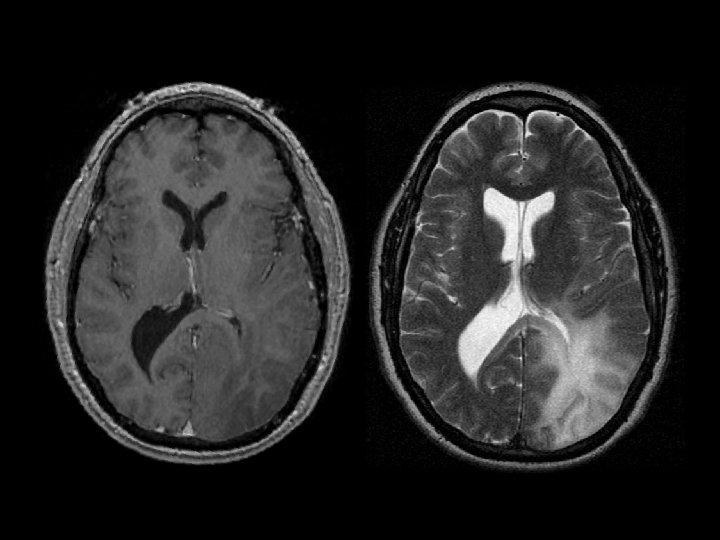

TB meningitis • Findings: – High attenuation of the cerebellar folia • Look for the primary site (lungs); usually a post-primary infection • Long and protracted illness rather an typical sx of acute bacterial meningitis • Look for BASAL involvement • ddx: – Carcinomatous meningitis – Sarcoidosis – Lymphoma – Subarachnoid blood